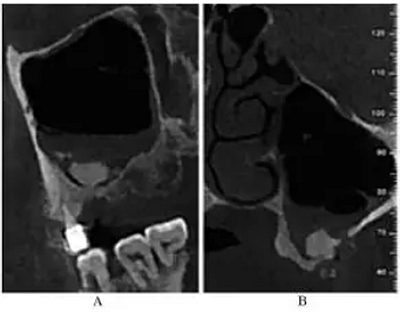

CBCT示:上頜竇內見液平面約達竇腔1/3(考慮為沖洗液未吸干凈),上頜竇垂直高度得到補足,26牙高度8.4mm,27牙高度為9.5mm(圖3)。患者拒絕穿刺液送病理檢查。

圖3 上頜竇外提升術后CBCT。

注:A,矢狀面;B,26頰舌向切面;C,27頰舌向切面;D,28頰舌向切面。